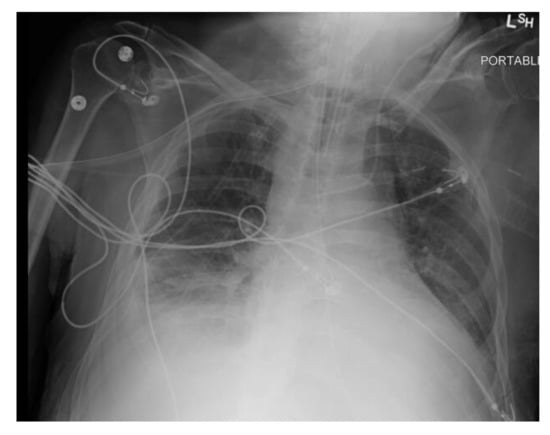

Initial laboratory studies showed elevated white blood cells (WBC) 22.6 × 109/L with neutrophilia, bicarbonate 21 mmol/L, lactic acid 6.5 mmol/L, anion gap 17, ALT 71 IU/L, AST 69 IU/L, and ALP 450 IU/L. ECG showed atrial fibrillation with a rapid ventricular response. CXR showed acute right pleural effusion (Figure 1). The patient was intubated for respiratory failure. He was also started on antibiotics (piperacillin-tazobactam and azithromycin) and intravenous normal saline with no improvement in blood pressure. The patient was then started on intravenous vasopressor support with norepinephrine and vasopressin and admitted to the intensive care unit (ICU).

Figure 1. CXR showing acute right pleural effusion.